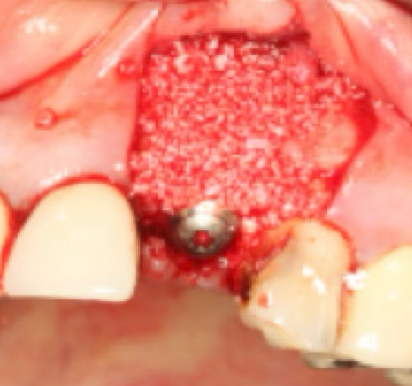

4단계: 뼈이식 완료

빈공간에 뼈이식재로 완벽하게 채워진 상태

중요: 1-2mm 이상의 간격(gap)는 반드시 뼈이식이 필요합니다

- ✓뼈이식을 통해 안정적인 골유착과 임플란트 성공률 향상

- ✓적절한 뼈이식으로 장기적인 안정성 확보